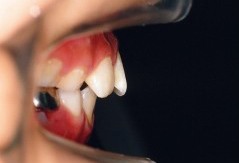

叢生(埋伏歯)

治療前 正面

乱杭歯になっています

治療前 上顎

乱杭歯及び歯が一本埋伏しています